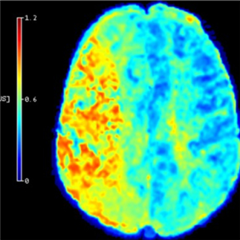

Améliorer la prise en charge des AVC

Une équipe du Centre de recherche en acquisition et traitement de l'image pour la santé a développé une méthode qui permet, à partir des images d'IRM de patients ayant subi un AVC d’améliorer l’évaluation des zones du cerveau pouvant récupérer après un traitement de reperfusion. Ces résultats, qui ouvrent la voie à une meilleure prise en charge des patients, en particulier de ceux jugés parfois inéligibles à ce genre de traitement, sont publiés dans la revue Stroke.